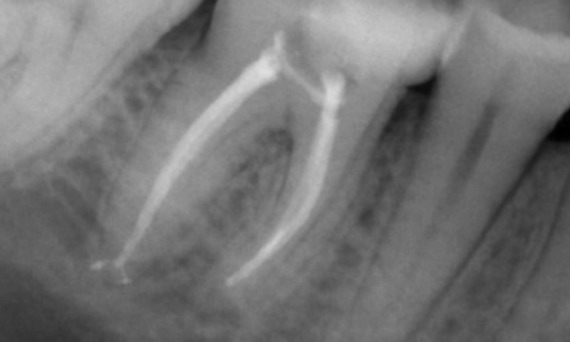

Un caso complejo con raíces largas y un sistema calcificado con un seguimiento de 14 meses

"Un éxito centrado en el paciente y el proceso". - Dr. Cowie

Antes: Radiolucencia periapical asociada principalmente con la raíz distal y pérdida de la lámina dura en la raíz mesial.